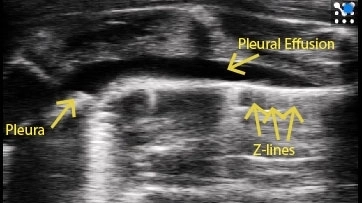

Pleural effusion can be seen along with B-lines coming down from the pleura.

Image courtesy of M.Sc. Niklas Hegemann, Kübler lab, Institute of Physiology, Charité-Universitätsmedizin Berlin & Dr. Jana Grune, Nahrendorf lab, Center for Systems Biology, Massachusetts General Hospital.